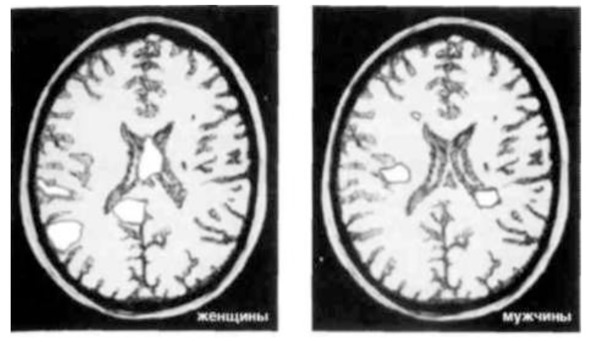

Фишер и Браун, вместе и по отдельности, проанализировали результаты сканирования мозга более 3000 «безумно влюбленных» студентов, полученные в тот момент, когда им показывали фотографии любимых. Ученые обнаружили, что у женщин, принимавших участие в исследовании, проявлялась повышенная активность базальных ядер – области мозга, связанной с памятью, эмоциями, вниманием, «центром удовольствий», а также участвующей в формировании ментальных образов и воспоминаний. Эта часть мозга отвечает за подсознание и первобытные инстинкты, она гораздо сильнее рациональной, мыслящей части – коры. Вот почему влюбленные ведут себя иррационально.

Мужчины, участвовавшие в исследовании, демонстрировали повышенную активность участка коры, отвечающего за визуализацию, и зон, связанных с обработкой зрительных образов, а также области, отвечающей за сексуальное возбуждение.

На снимках – результаты исследования, проведенного доктором Брауном. Показаны сканы мозга мужчин и женщин, которые смотрят на фотографии людей, в которых они страстно влюблены. На них хорошо видно, что у мужчин и женщин активизируются разные участки мозга.

На Рис.1 видно, что у мужчин светлых участков меньше, чем у женщин, но если смотреть на снимки в цвете, то заметно, что активизированные участки у мужчин более интенсивно окрашены.

Таким образом, на ранней стадии влюбленности у мужчин главный инструмент оценки сексуального потенциала женщин – глаза.

Женщины же оценивают потенциал мужчины в качестве долгосрочного партнера, опираясь при этом на память.

Рис.1